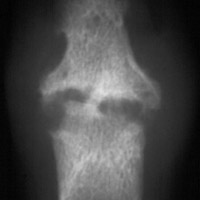

Gout: Erosion in both head of proximal phalanx and base middle phalanx 2nd toe with normal joint space

++